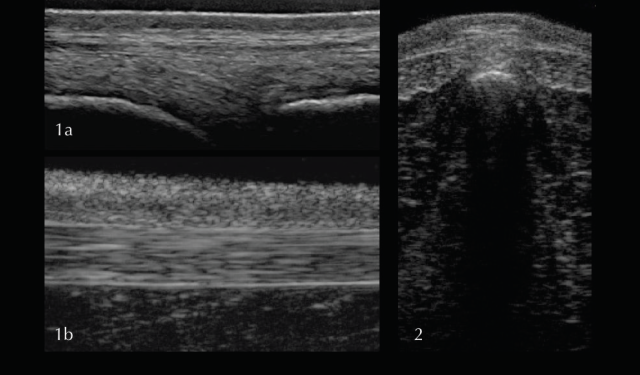

For the supra- and interspinous ligaments (SSL and ISL) longitudinal views are most useful. The images are best acquired with a high-frequency linear transducer using a stand-off pad. The head should be kept in a neutral position as high head carriage may cause relaxation of the SSL and therefore a hypoechogenic appearance. Superficial fibres of the SSL have a horizontal orientation whereas deep fibres of the ISL run in caudoventral direction appearing hypoechogenic in comparison. Care should be taken to position the probe exactly midline at the level of the dorsal spinous processes. The aponeuroses of the epaxial musculature can be imaged off-midline with a parallel fibre pattern similar to the SSL.

In the thoracic (saddle) region the SSL is thin and wide, whereas further caudal in the lumbar region the ligament is thick and narrow with a more echogenic, homogenous appearance. The transverse view of the SSL is less useful due to being more prone to artifacts. In order to achieve the best image quality, the transducer should be tilted cranially and caudally. Published scientific data about the ultrasonographic appearance of the SSL in normal horses and horses with back pain offering information about the potential clinical significance is limited (Henson et al 2007). The clinical significance of heterogenous regions in the SSL should therefore be questioned and further tests, such as diagnostic local anaesthesia, should be applied.

Deep to the ligament the fibrocartilaginous cap, visualised as a hypoechogenic line of approximately 1mm, is visible and runs parallel to the hyperechoic line of the DSP bone surface. The ISS cannot be assessed fully and a statement about potential iminging DSPs should not be made based on ultrasonography alone. The intervertebral articulations can be examined ultrasonographically, both in sagittal and frontal planes, using a convex transducer (Denoix 1999a; Reisinger and Stanek 2005).